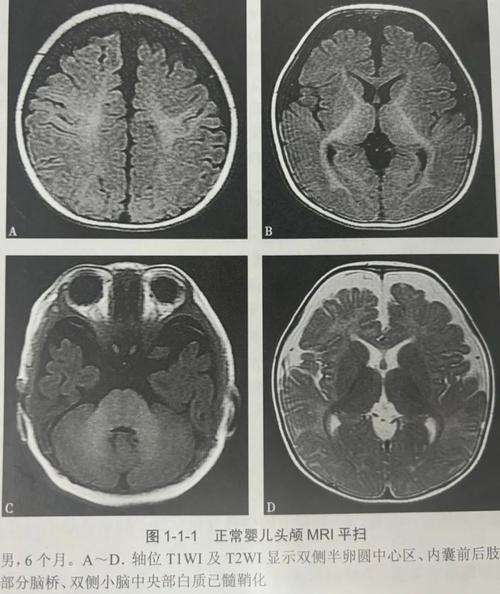

(图片来源网络,侵删)- MRI能非常清晰、精细地显示大脑、脊髓、肌肉、关节、内脏器官等软组织的结构。

- 对于新生儿来说,很多疾病都与脑部发育、神经损伤或内脏结构异常有关,MRI是观察这些结构的“金标准”。